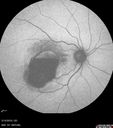

62 year old african american female with moderate chronic hypertension A few weeks ago she was at work and noticed a dark spot in the right eye. Since then it is not getting any better. She was out of town when it happened. VA OD: Dcc6’/200 Ncc20/400 VA OS: Dcc20/32 NccJ1

Macroaneurysm - Macular Hemorrhage - Branch Retinal Aterial Occlusion377 views62 year old African American female with chronic hypertension and vision loss for 2 weeks. VA is 20/40000000